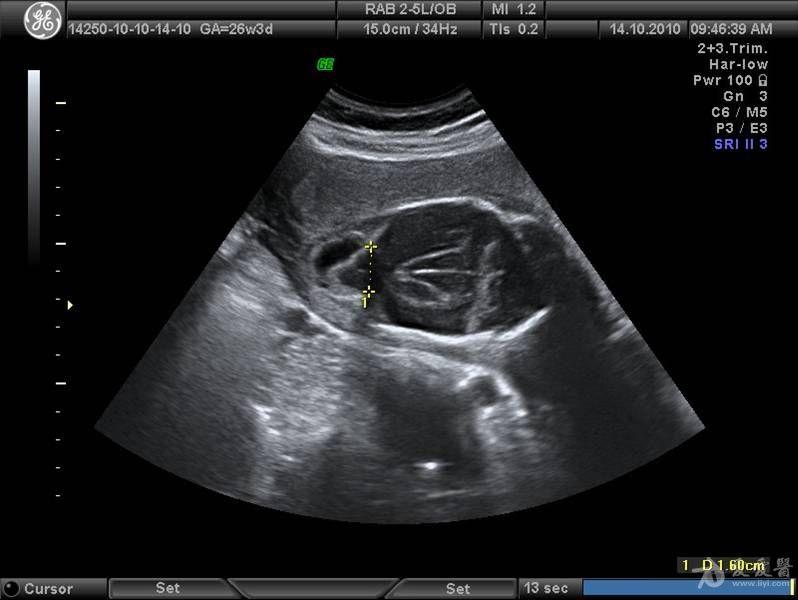

胎儿成人型多囊肾

图片尺寸720x480